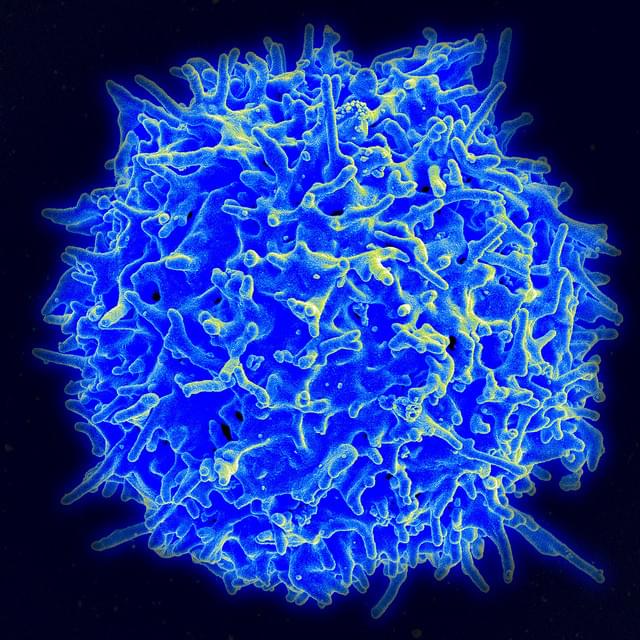

Signaling is fundamental to how cells sense and respond to their environment—but in immune cells, those signals must be precisely amplified to mount an effective defense against invasive threats. New research by immunologists in Germany is shedding light on how that amplification occurs in T cells, revealing a key molecular mechanism that helps trigger immune responses—and may also contribute to inflammatory conditions.

Writing in Science Signaling, researchers at the University Medical Center Hamburg-Eppendorf identified a crucial step in the production of a “second messenger,” an internal signal that relays and amplifies messages received at the cell surface. Because external signaling molecules cannot enter the cell, second messengers translate those cues into powerful intracellular responses.

In T cells, that process depends on NAADP (nicotinic acid adenine dinucleotide phosphate), a molecule that drives calcium (Ca²⁺) signaling—an essential step in T cell activation. Without it, T cells cannot become the effector cells needed to fight serious threats, such as infections or cancer.